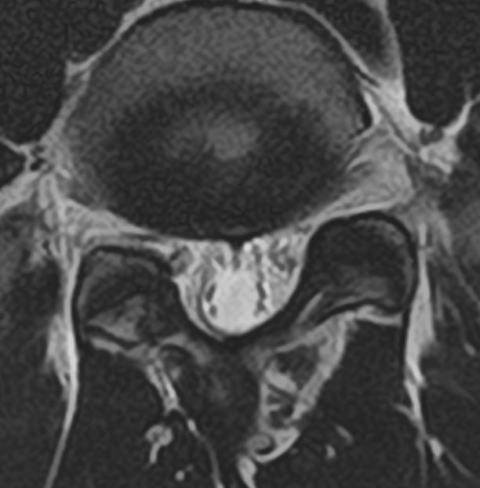

MRI T2強調像

MRI Bone like image

CT いずれも腰椎右椎弓の分離症

MRI、CTどちらも長所、短所があります。もう少しCTと比較してMRIのBone like imageの解像度が上がれば良いかなと思います。